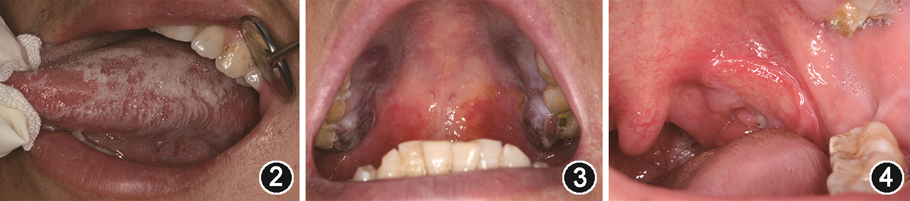

(2)毛状白斑(hairy leukoplakia):毛状白斑是患者全身免疫严重抑制的征象之一,主要见于HIV感染者,少数可见于血液恶性肿瘤、骨髓或器官移植、长期使用糖皮质激素的患者[10]。毛状白斑的发生与EB病毒感染有关[5],最初多见于男性同性恋者。临床表现为双侧或单侧舌缘无症状的白色斑块,表面粗糙或呈皱褶状,不能被擦去(图2)。在少数情况下,颊、软腭、咽部或食道也可受累。

(4)卡波西肉瘤(Kaposi sarcoma):卡波西肉瘤是HIV感染者中最常见的口腔恶性肿瘤,是AIDS的临床诊断指征之一,其发生主要与人类疱疹病毒8型(human herpes virus,HHV-8)感染有关[11]。好发于腭和牙龈,呈单个或多个褐色或紫色的斑块或结节,可有分叶,伴溃烂或出血(图3)。该病发病部位广泛,进展迅速,恶性程度高,其预后取决于机体的免疫功能、疾病所处的阶段、有无机会性感染等因素[9]。

(5)HIV相关性溃疡:HIV感染者可发生无明确原因的非特异性口腔溃疡,病损范围较大,不易愈合[5]。HIV相关性复发性阿弗他溃疡表现为口腔黏膜出现单个或多个反复发作的圆形或椭圆形疼痛性溃疡(图4),占HIV相关性口腔病损的7%左右[6]。